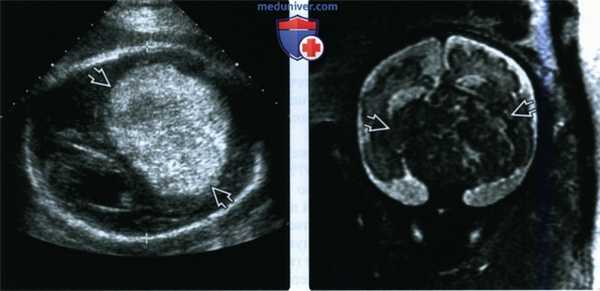

(Слева) При УЗИ головного мозга плода в поперечной плоскости визуализируется гомогенное гиперэхогенное новообразование. Картина при УЗИ в режиме серой шкалы напоминает таковую при внутричерепном кровоизлиянии, поэтому необходимо подтверждение диагноза с помощью допплеровского УЗИ.

(Справа) При МРТ на Т2-ВИ в сагиттальной плоскости у этого же плода видно преимущественно солидное супраселлярное новообразование, дающее сигнал низкой интенсивности. Опухоль была краниофарингиомой, но при лучевой диагностике ее невозможно было отличить от тератомы.